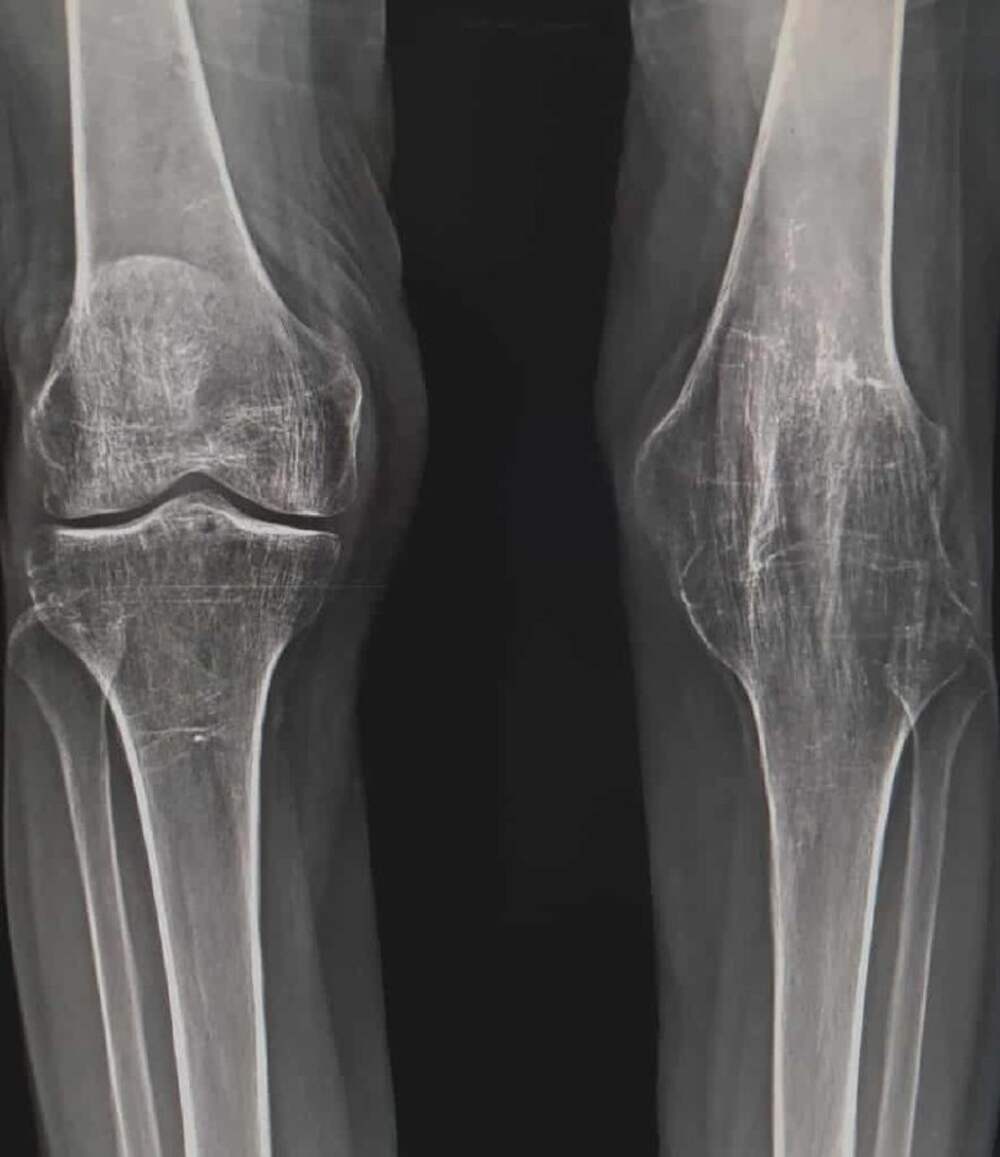

Анкилозом называют полную неподвижность сустава, вызванную фиброзной или костной спайкой сочленяющихся костей. https://travmakab.ru/travma/242